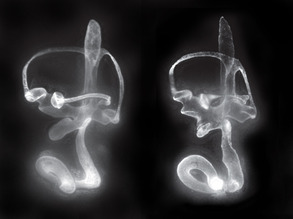

Daydreams

Schizophrenia Awareness Week